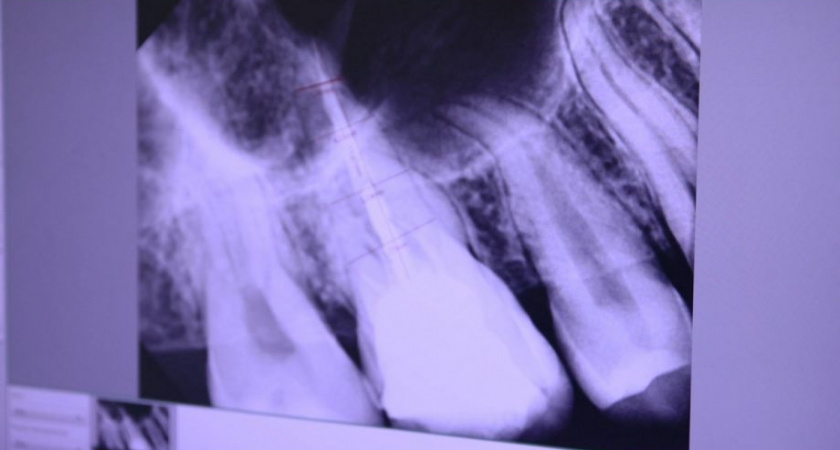

В Петропавловске-Камчатском в городскую стоматологическую поликлинику поступил новый рентгеновский датчик, который повысит точность диагностики и упростит работу врачей. Об этом сообщил заведующий городской стоматологией Денис Изюмский. «Новый рентгеновский датчик Vatech EzSensor HD 1.5. компактный, но высокоэффективный. Этот датчик значительно упростит работу врачей и улучшит диагностику, так как требует минимального уровня рентгеновского излучения. Основная функция датчика заключается в том, что полученное изображение передается на компьютерный монитор, а затем быстро распространяется по всем рабочим станциям. Это позволяет врачам проводить диагностику без задержек, что существенно экономит время. Устройство позволит проводить измерения и настраивать различные экспозиции, что улучшает работу специалистов. С высоким разрешением аппарата врачи могут выявлять даже самые мелкие дефекты, что повысит точность диагностики», - сообщил Денис Изюмский. В поликлинике активно исследуются новые технологии и методы лечения, диагностики и обследования. Радиовизиограф нового поколения основан на технологии CMOS APS (Active Pixel Sensor), что позволяет получать чёткие и контрастные изображения с высоким разрешением. Высокое качество снимков обеспечивает надежную диагностику и эффективное планирование лечения. Об этом сообщили ИА «Камчатка» в пресс-службе правительства края. Положительным опытом после прохождения процедуры поделился пациент Михаил. «Проходил обследование в стоматологической больнице с использованием нового рентгеновского датчика. Процедура прошла комфортно. Теперь возможно быстро пройти обследование, получить точный диагноз и сразу приступить к лечению. Рекомендую всем не бояться посещений стоматолога, ведь современные технологии делают процесс обследования безопасным», - рассказал Михаил. Отметим, оборудование было приобретено за счёт средств обязательного медицинского страхования.